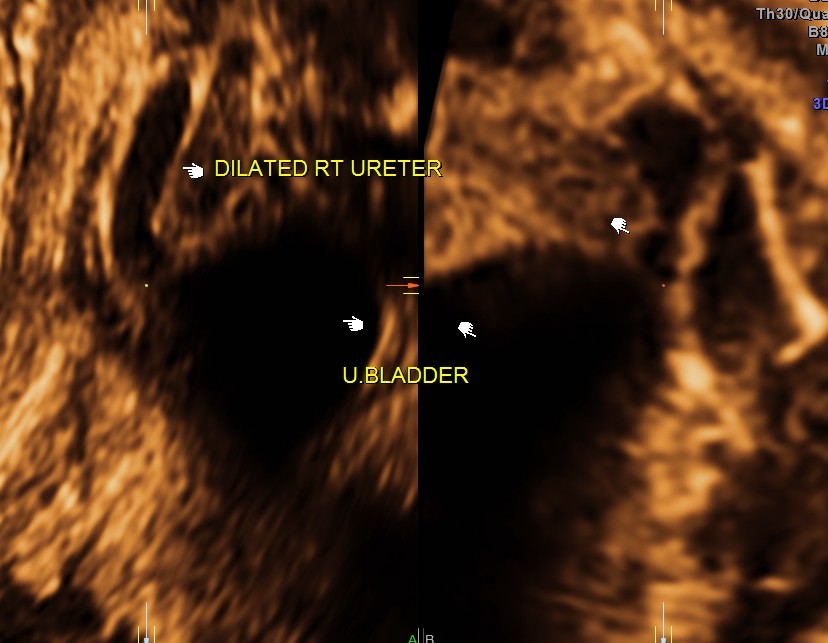

3 d reconstruction shows an echogenic tissue at the junction of ureter and bladder.

rendered image of the same

Right sided hydro uretero nephrosis , with likely obstruction at right vesico ureteric junction.